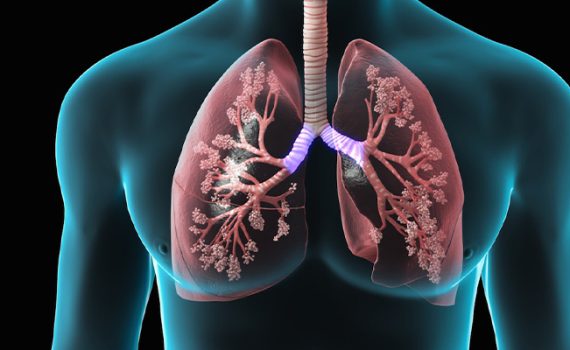

Пульмонология

Отделение пульмонологии Международного госпиталя Актиф специализируется на диагностике, лечении и лечении заболеваний дыхательных путей. Мы оказываем квалифицированную помощь при широком спектре легочных заболеваний, от астмы и ХОБЛ до сложных легочных заболеваний, обеспечивая наилучшие результаты для наших пациентов.

Мы предлагаем полный спектр легочных услуг, включая проверку функции легких, бронхоскопию, лечение хронических заболеваний легких, легочную реабилитацию и лечение расстройств сна. Наше отделение оснащено всем необходимым для лечения как острых респираторных заболеваний, так и хронических болезней легких.

Передовые методы диагностики и лечения

Мы используем новейшие методы диагностики легких, включая передовые методы визуализации и современные тесты функции легких, для точной диагностики респираторных заболеваний. Варианты лечения варьируются от медикаментозного лечения до малоинвазивных процедур с учетом потребностей каждого пациента.